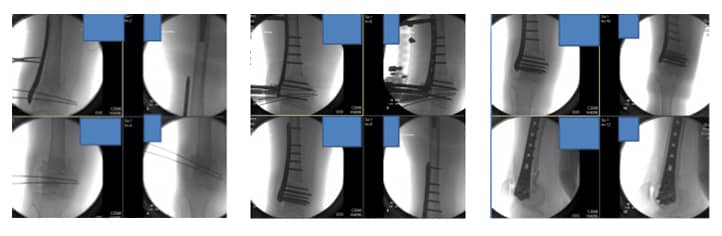

As imagens fluoroscópicas intraoperatórias mostram redução provisória inicial e redução final com fixação em placa LISS.